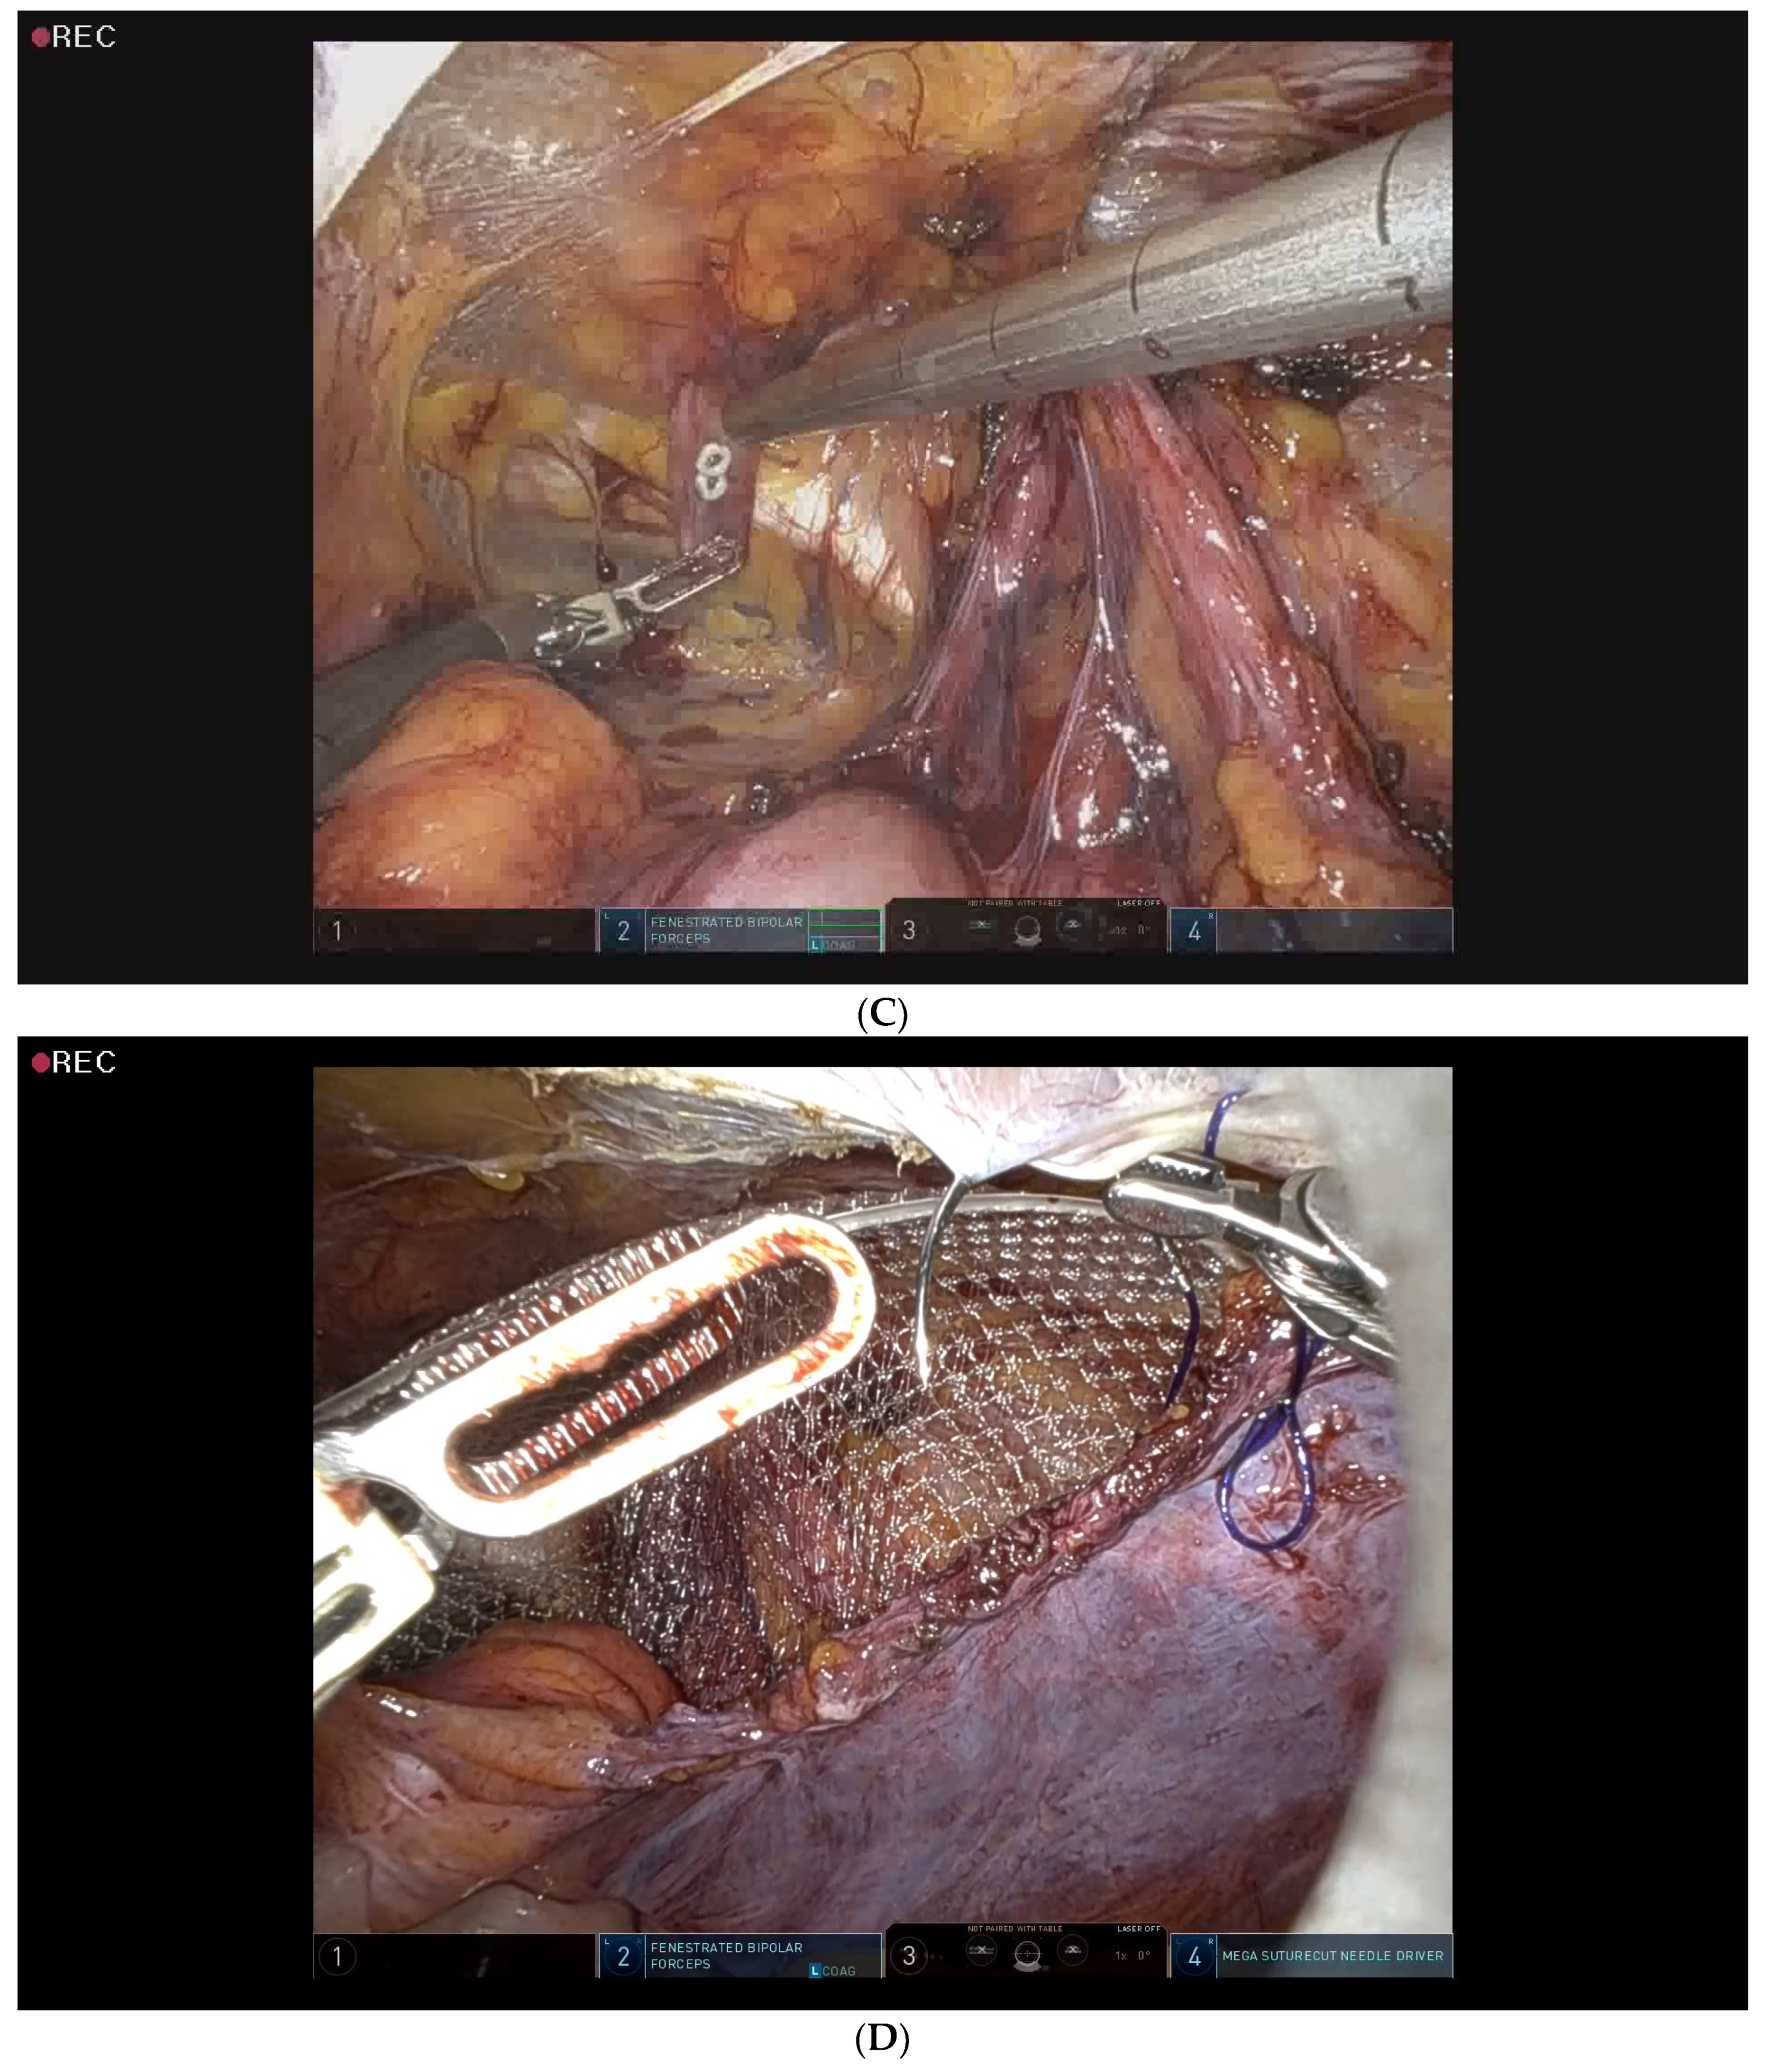

2.5. Surgical Procedure for Robotic-Assisted TAPP Inguinal Hernia Repair